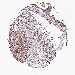

PANCREATIC CANCER - Protein expressioni

A mouse-over function shows sample information and annotation data. Click on an image to view it in a full screen mode. Samples can be filtered based on level of antibody staining by selecting one or several of the following categories: high, medium, low and not detected. The assay and annotation is described here.

Note that samples used for immunohistochemistry by the Human Protein Atlas do not correspond to samples in the TCGA dataset.

Antibody stainingi

Antibody staining in the annotated cell types in the current human tissue is reported as not detected, low, medium, or high, based on conventional immunohistochemistry profiling in selected tissues. This score is based on the combination of the staining intensity and fraction of stained cells.

Each image is clickable and will lead to virtual microscopy that enables deeper exploration of all samples and also displays staining intensity scores, fraction scores and subcellular localization as well as patient and tissue information for each sample.

Antibody HPA038061

Staining

High

Medium

Low

Not detected

Intensity

Strong

Moderate

Weak

Negative

Quantity

>75%

75%-25%

<25%

None

Location

Nuclear

Cytoplasmic/membranous

Cytoplasmic/membranous,nuclear

Adenocarcinoma, NOS